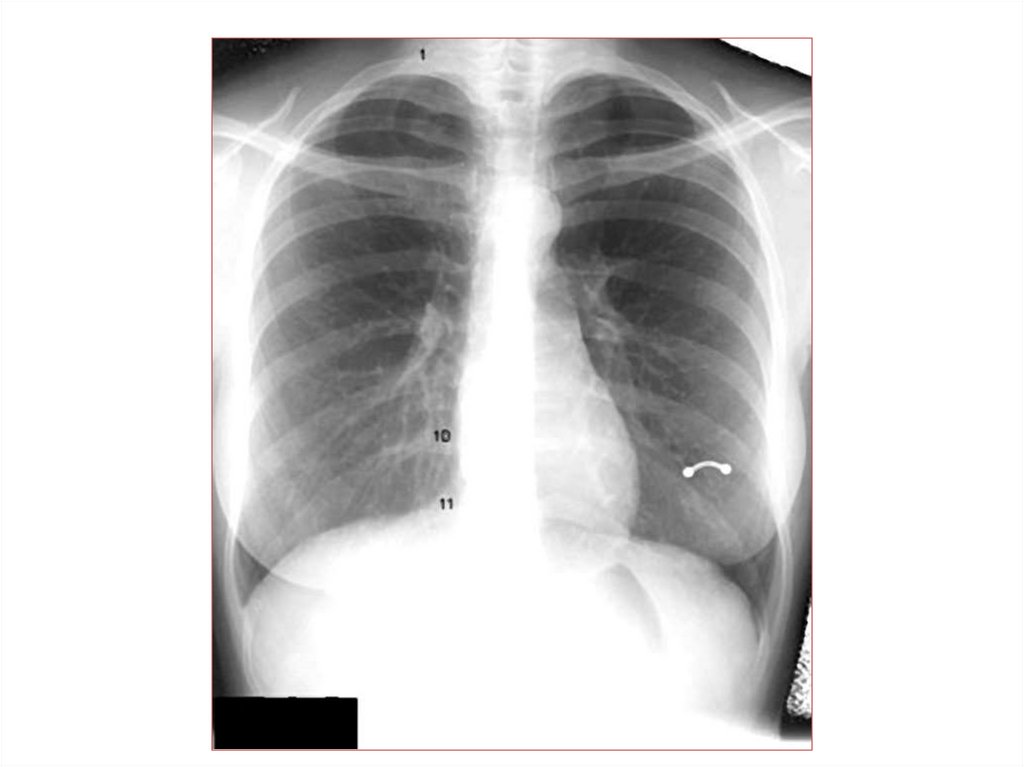

Пневмония